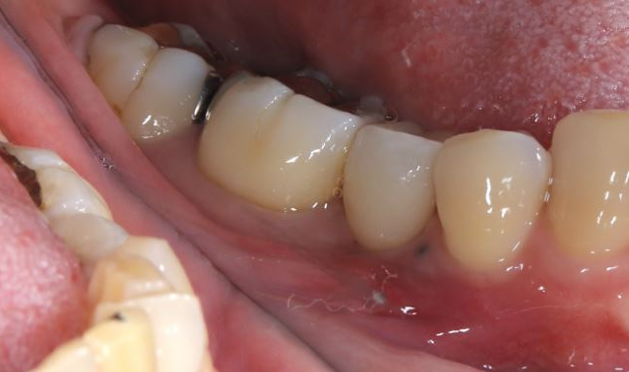

奥歯のインプラント症例⑥

治療前

治療後

治療内容

以前抜歯した部分にインプラントを入れました。副鼻腔粘膜を挙上して骨再生をしています。

期間 4か月

費用 税込90万円

起こりうる副作用・リスク 保険外治療です。

手術後にインプラントの定期メンテナンスを怠ってしまうと、インプラント周囲炎になるリスクが高まります。